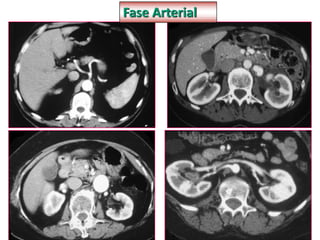

Fase Arterial